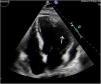

A 68-year-old male was admitted to the Intensive Care Unit due to an inferoposterolateral acute myocardial infarction (Killip class IV). Emergency coronary angiography revealed severe two-vessel coronary artery disease, subjected to angioplasty with the placement of drug-eluting stents. The patient exhibited moderate ventricular dysfunction, in addition to ischemic hepatitis and the need for renal replacement therapy. Control transthoracic echocardiography demonstrated the presence of a lateral aneurysm (Fig. 1, white arrow). The study was completed 7 days later with cardiac magnetic resonance imaging (Figs. 2 and 3). A giant pseudoaneurysm, measuring 90×60mm, was identified (black arrow), accompanied by severe ventricular dysfunction. A very wide neck was observed (suggestive of aneurysm), but without myocardial visualization in the lesion. Furthermore, the lesion demonstrated rapid expansion over the course of one week, suggestive of a pseudoaneurysm. The reference center confirmed the diagnosis and initiated a pre-transplantation evaluation of the patient.